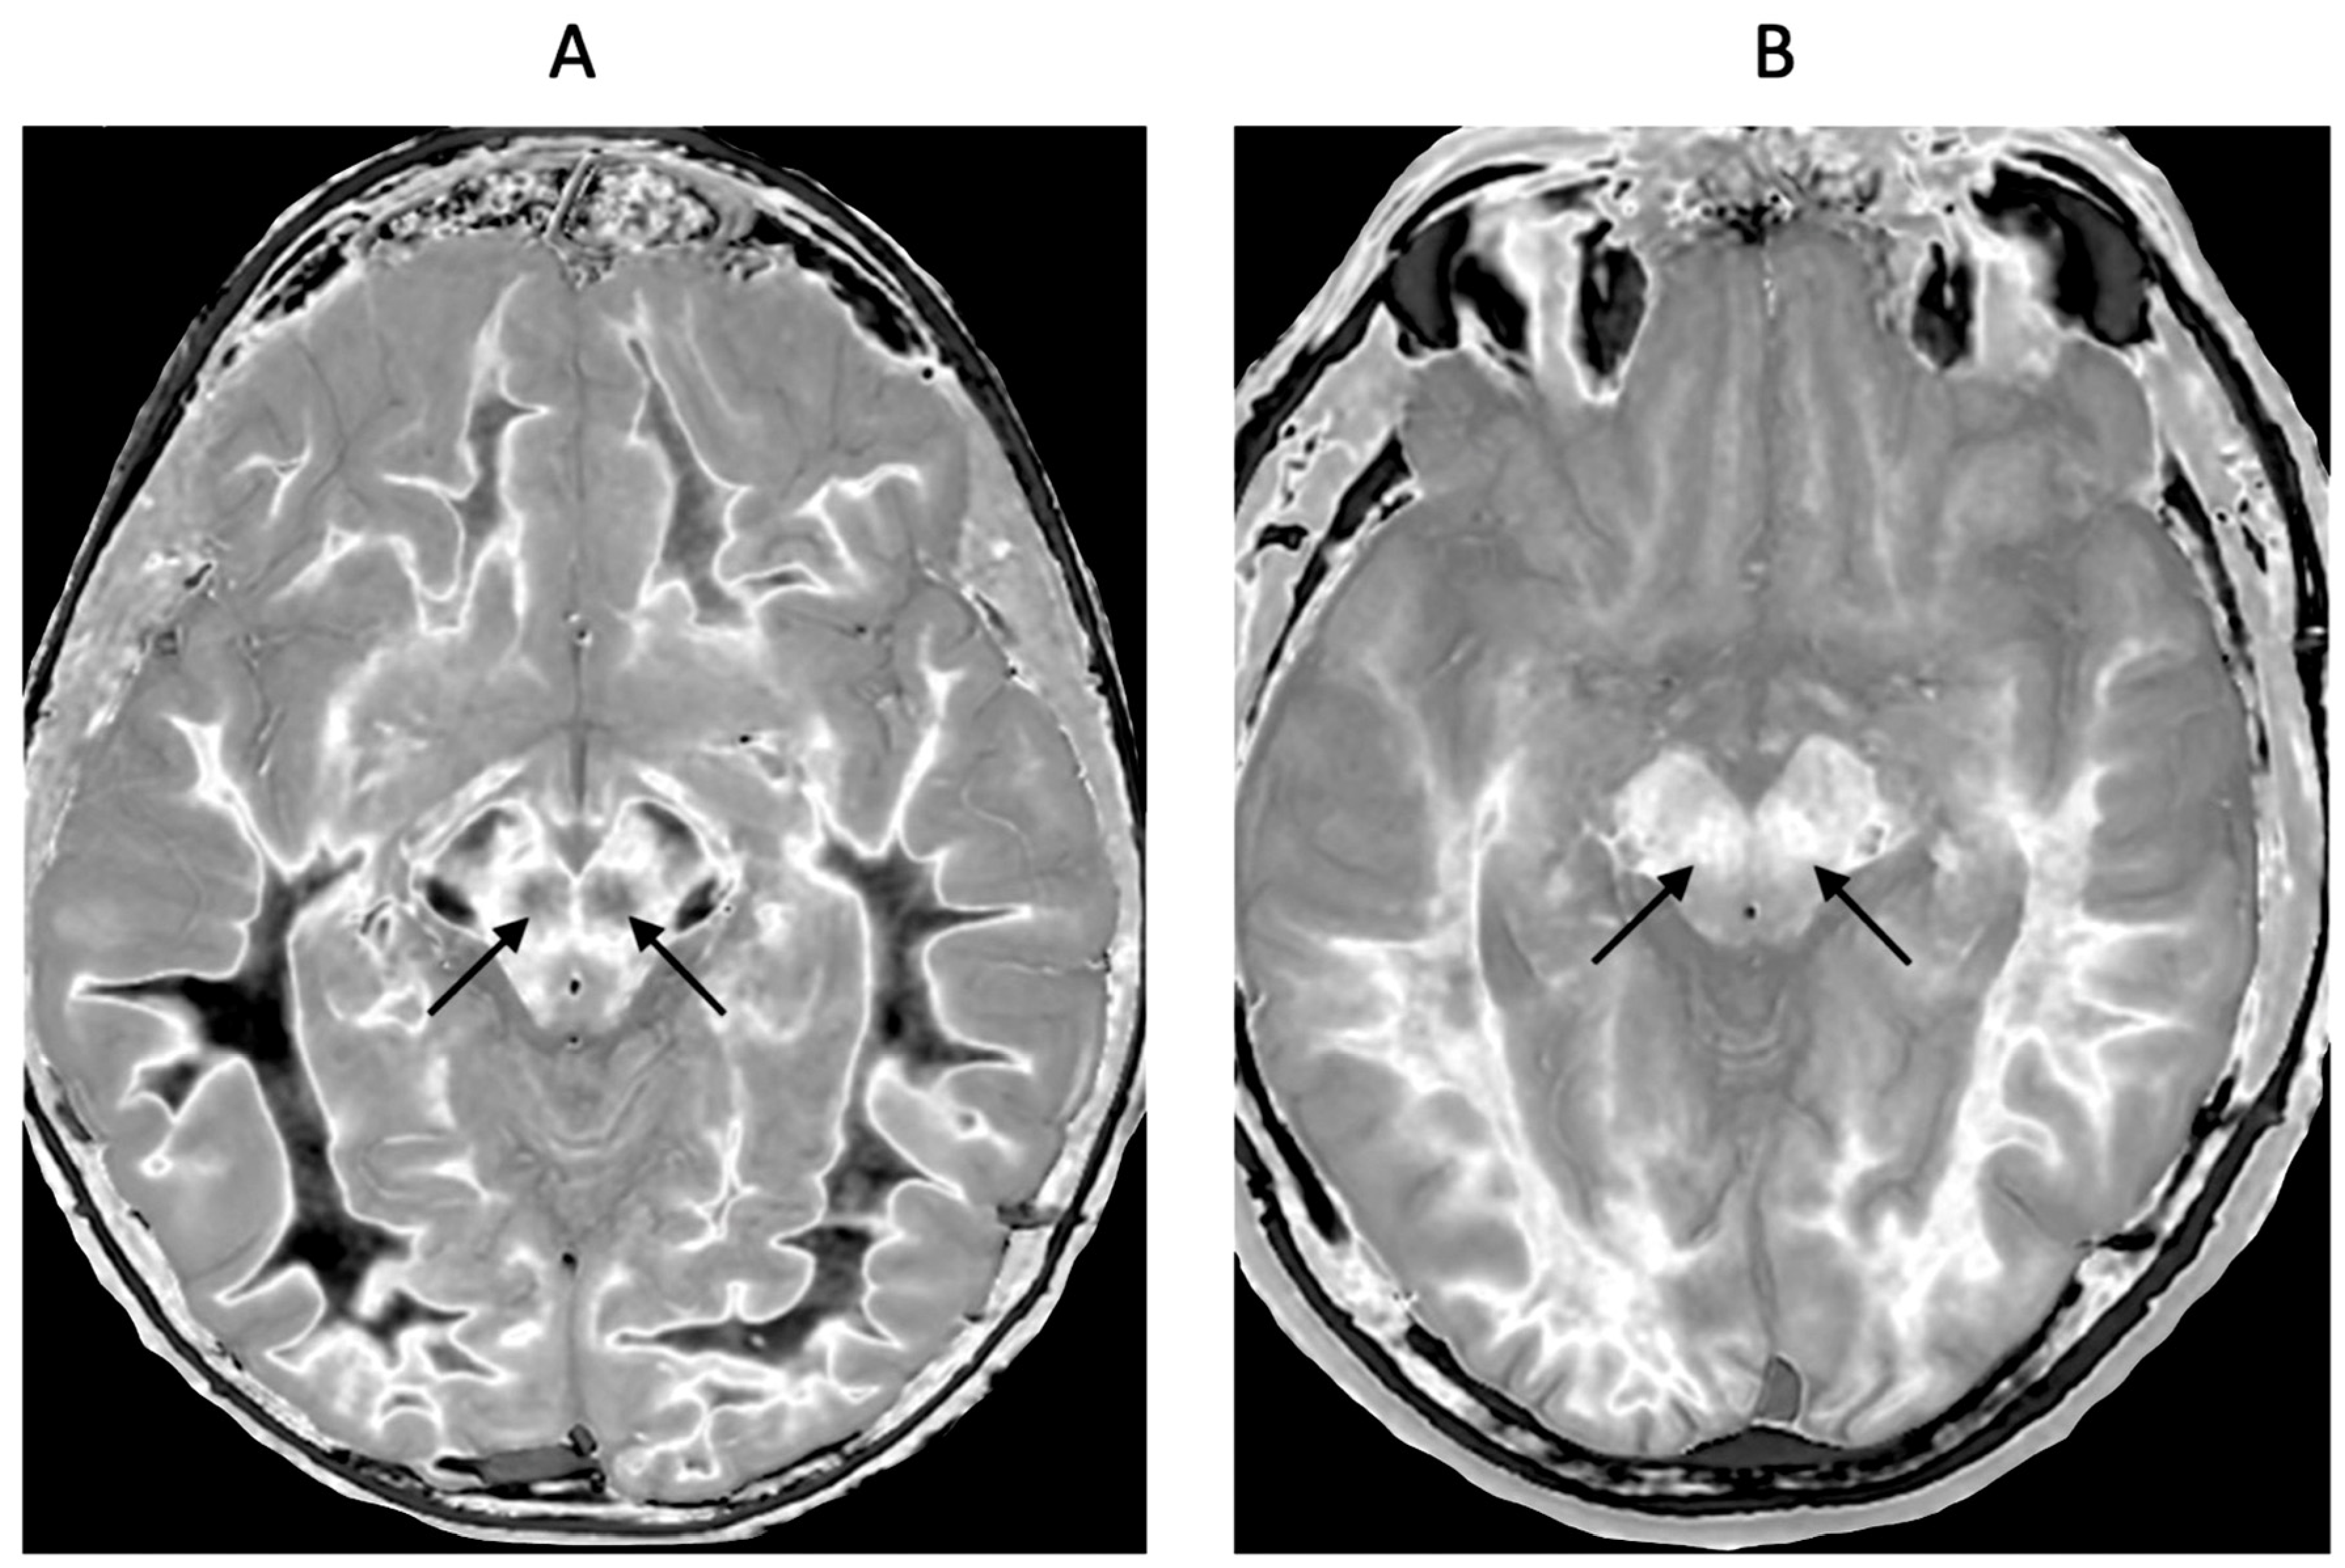

Figure 14.

Red nuclei in an 18-year-old normal control (A) and an 18-year-old male patient with mTBI (B). 2D narrow mD dSIR images. In (A) the normal control shows low signal in the white matter of the cerebral hemisphere, cortical spinal tracts and the ascending sensory tracts. The red nuclei (arrows) have an intermediate mid-gray signal. In (B) the patient shows high signal in the cerebral white matter, the corticospinal tracts and the ascending sensory tracts (whiteout sign, grade 4 out of 5). In addition, the red nuclei are higher signal than in (A) (arrows). No abnormality was seen on the T2-FLAIR images in the normal control or patient.